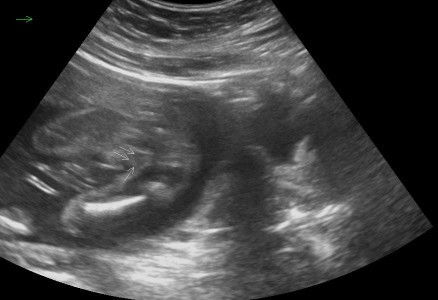

Hai mummys..sy nk tny klau mcm ni konfem girl ke? sy scan mse 21 weeks di Sonobee..agak2 ad xyg scan girl tiba2 keluar boy? #seriusnanya #ingintahu

gmbr xjelas sbb ada halangan pd bhgn celahan kaki. repeat semula utk double confirmation

mcm xjelas sgt tu sis..Dr ckp girl ke?

ye sis..sono tu ckap girl..